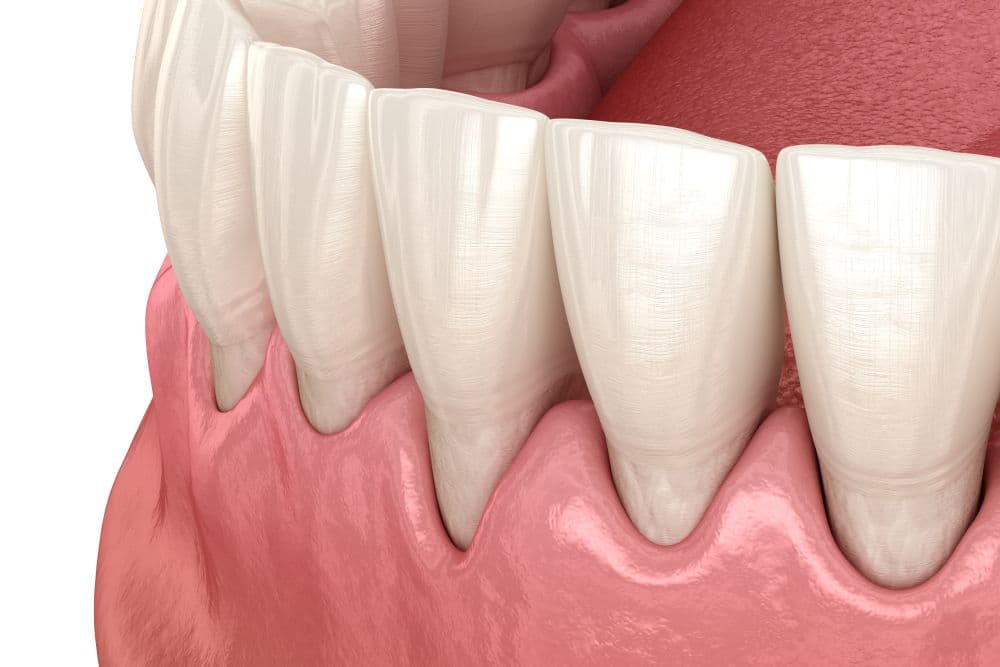

Parodontologie is de leer van de ziekten van het parodontium. Het parodontium is het weefsel rond de wortels van tanden en kiezen. Het omvat de gingiva, het parodontale ligament, het wortelcement en het alveolaire bot. Gingiva is een ander woord voor tandvlees. Het parodontale ligament zijn de bindweefselvezels tussen enerzijds de wortel van de tand of kies en anderzijds het kaakbot. Het wortelcement is een laagje op de wortel waarin de vezels van het parodontale ligament vast zitten. Het alveolaire bot is een ander woord voor kaakbot.

Parodontitis

Ontstoken tandvlees heet parodontitis wanneer niet alleen het tandvlees is ontstoken maar ook het onderliggende kaakbot. Door de ontsteking laat het tandvlees los van de tanden en kiezen, waardoor er een ruimte tussen het tandvlees en de wortel ontstaat. Deze ruimte heet een pocket. In deze pocket gaan tandplak en tandsteen met z’n bacteriën zitten waardoor de ontsteking zich langzamerhand in de diepte verplaatst en daar het omringende kaakbot afbreekt. Het is meestal een chronische, sluimerende ontsteking die vaak al jarenlang aanwezig is zonder dat er pijnklachten zijn.

Net zoals bij gingivitis bloedt het tandvlees bij aanraking, is rood en gezwollen en men heeft vaak last van een vieze smaak en een slechte adem. Door roken worden deze kenmerken vaak weer gemaskeerd. Pas in een vergevorderd stadium ontstaan er klachten. De tanden en kiezen gaan los staan omdat er onvoldoende kaakbot rond de wortels aanwezig is. Wanneer met het kaakbot ook langzamerhand het tandvlees terug gaat trekken, liggen de worteloppervlakken gedeeltelijk bloot waardoor de tanden en kiezen erg gevoelig zijn voor temperatuurwisselingen en zoet en zuur. In het eindstadium van parodontitis is er zoveel kaakbot verloren gegaan dat de tanden en kiezen vrijwel vanzelf uit de mond vallen.